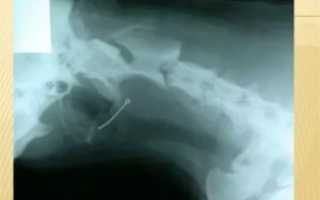

В большинстве случаев бывает сложно определить место локализации кости. Если она застряла между ротоглоткой и гортаноглоткой, то возникают не локальные, а разлитые болевые ощущения. Чтобы обнаружить кость в пищеводе, необходимо провести эндоскопическое исследование.